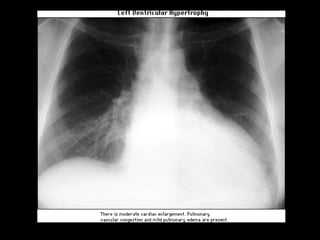

CRECIMIENTO DEL VENTRÍCULO IZQUIERDO Proyección PA Prominencia exagerada del arco inferior del perfil izquierdo:  Puede ser redondeado ( hipertrofia ) ó elongado ( dilatación) Proyección OAI El arco inferior rebasa la mitad anterior de la columna El ángulo que forma con el hemidiafragma izquierdo  Puede ser agudo  (hipertrofia ) u obtuso ( dilatación) Proyección Lateral El perfil del Ventrículo Izquierdo se desplaza hacia atrás de la VCI

CRECIMIENTO DEL VENTRÍCULOIZQUIERDO Proyección PA Prominencia exagerada del arco inferior del perfil izquierdo: Puede ser redondeado ( hipertrofia ) ó elongado ( dilatación) Proyección OAI El arco inferior rebasa la mitad anterior de la columna El ángulo que forma con el hemidiafragma izquierdo Puede ser agudo (hipertrofia ) u obtuso ( dilatación) Proyección Lateral El perfil del Ventrículo Izquierdo se desplaza hacia atrás de la VCI